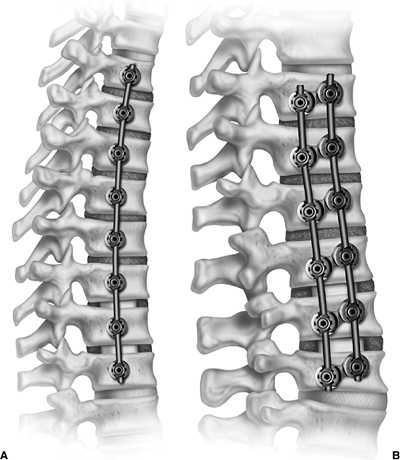

![]()  |

Figure 18.1 A:

This 16-year-old girl with severe scoliosis refused early treatment and had severe progression. Her clinical examination demonstrated marked trunk and rib deformity, and she had reduced pulmonary function. B: The posteroanterior radiograph demonstrates a right thoracic curvature of 125 degrees. With proper diagnosis and early treatment, deformity such as this should be completely avoidable in AIS.  |